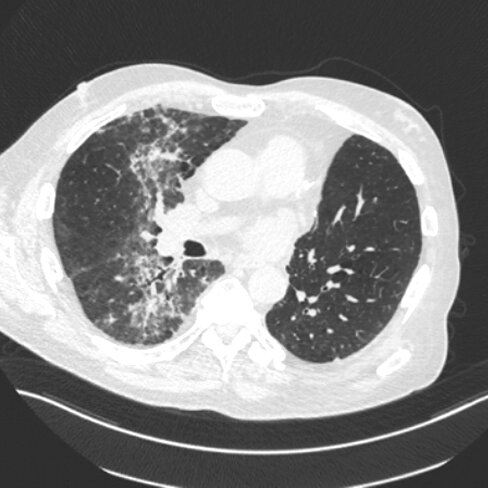

23F p/w several years of persistent productive cough and recurrent acute bronchitis. She reports nasal congestion with postnasal drip, as well as weight loss, and frequent bulky foul-smelling stool. She had one previous hospitalization for pneumonia.

Vital signs are normal. Lung auscultation reveals bibasilar crackles. Clubbing is present.

CXR reveals increased interstitial markings with peribronchial thickening and dilatation.

Diagnosis?

What is: cystic fibrosis